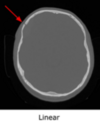

What is a linear skull fracture, and what does it look like on CT head?

Linear skull fracture: Straight, non-displaced break in skull bone Usually causes minimal brain damage CT finding: Thin line interrupting the cortical outline of skull bone